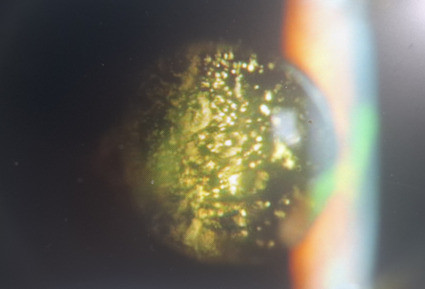

星狀玻璃體的病變,有很明顯的星狀沉積物漂浮在玻璃體中。(達特楊眼科提供)

此外,於晚上或關燈後,在燈下或以手電筒見到瞳孔的中央有上百成千星狀或雪花狀混濁點漂浮物,如聖誕節的飾物般閃爍,這就是星狀玻璃體的病變,此種混濁小點包含有鈣鹽或脂質的沉積物,漂浮於玻璃體中,患者本身無自覺症狀,也不影響視力,年齡越大者越常見,無特殊治療方法。一旦發現有星狀玻璃體,40%合併糖尿病,33%為高膽固醇,而44%的患者其三酸甘油脂值大於190 mg/dl,另外酗酒容易產生。